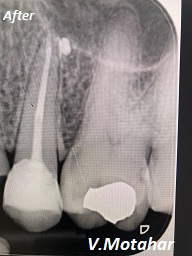

Root Canal treatment on Lower molar tooth immediate after the Root Filling!

before

after

Root canal treatment on three rooted tooth! which had 4 canals!